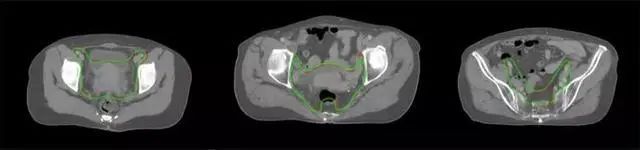

四、放射治療智能勾畫軟件

放射治療,簡稱放療,是治療腫瘤主要手段之一,利用放射線破壞照射區(qū)(靶區(qū))的細胞,使腫瘤細胞停止分裂直至死亡,醫(yī)生通常把放射治療形象的比喻為“打靶”,放療前精準勾畫腫瘤靶區(qū)范圍是腫瘤放射治療的關鍵步驟。傳統(tǒng)的靶區(qū)勾畫醫(yī)生會根據(jù)患者多張CT、MRI影像片憑借經(jīng)驗進行,比較耗時,治療的病人數(shù)量也有限,且靶區(qū)勾畫缺少行業(yè)統(tǒng)一的規(guī)范和標準,無法達到同質(zhì)化,勾畫精確度不理想。

技術(shù)原理

基于深度學習人工智能的放療靶區(qū)智能勾畫技術(shù)和自動計劃技術(shù),基于全面的市場調(diào)研和臨床專業(yè)意見,采用獨創(chuàng)的基于小樣本量的人工智能算法,實現(xiàn)放療靶區(qū)和危及器官的快速全自動勾畫。

產(chǎn)品優(yōu)勢

縮短至幾分鐘內(nèi)便可完成,大幅提升了放療效率,且人工智能平臺完成的靶區(qū)勾畫可基本滿足臨床醫(yī)生需求,專家只需審核時細微調(diào)整,可顯著提高靶區(qū)勾畫的規(guī)范化及精準度,讓放療智能化,標準化??筛采w食管癌、鼻咽癌、直腸癌、宮頸癌、肺癌等多種病種。